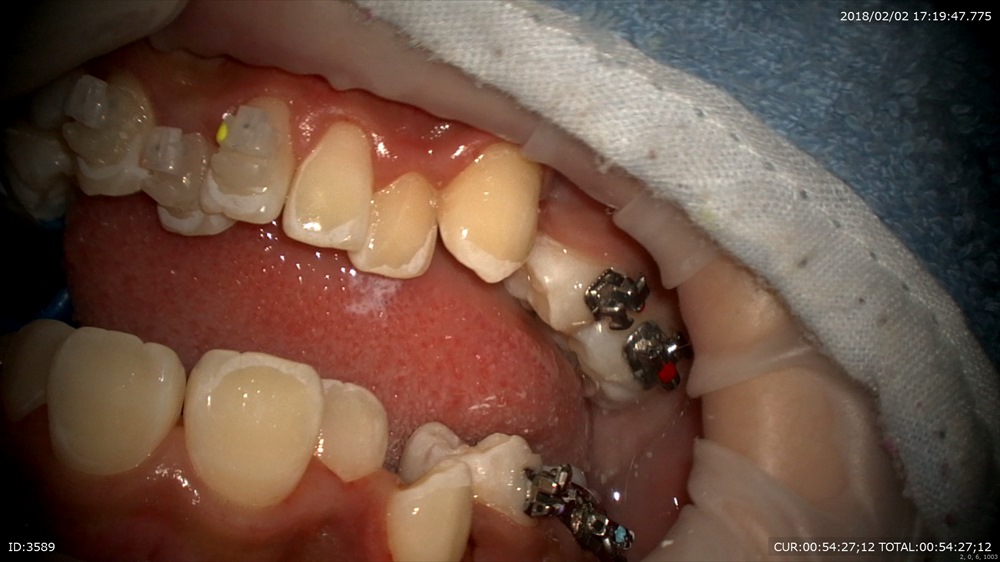

矯正から。今日が装置装着の初日。当院は通常分ける作業を1日で、すべてやります。抜歯→TPA装着→DBS→ワイヤー装着

TPA装着、DBS

デーモンシステム。こうする事で矯正期間の短縮と痛みの軽減につながります。綺麗になるのを楽しみに!!